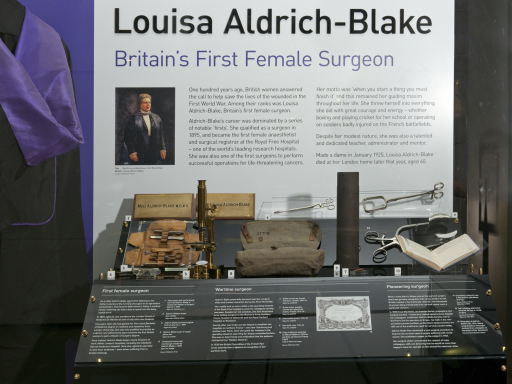

Curator Helen Peavitt and Stephanie Millard uncover the life of Dame Louisa Aldrich-Blake, Britain’s first female surgeon.